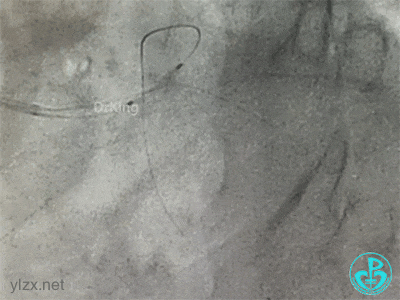

导丝准备穿支架网眼Rewire回旋支时患者血压继续下降。去甲肾上腺素微量泵剂量逐渐增大至25ml/h,立即置入IABP,血压回升后再继续操作。

导丝Rewire回旋支,非顺应性球囊分别后扩张前降支和回旋支支架,对吻扩张。

患者术中血压偏低,一度出现烦躁。及时IABP置入是手术能顺利完成的保障。术前的准备很全面,造影结果如下。